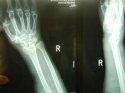

上一期绿巨人视频污版app最新版讲诉了患桡骨远端骨折的原因及其注意事项, 绿巨人视频app黄色官方下载仪品牌 绿巨人视频污版app最新版继续为您讲述桡骨骨折后如何更好的恢复。 1、俗话说伤筋动骨一百天,有钢板的在1年内每月到医院复

桡骨是人体前臂双骨之一,位于前臂外侧,大拇指一侧,分为一体和两端。是前臂长骨之一;蛙、蟾蜍等动物的桡骨与尺骨愈合成桡尺骨。 绿巨人视频app黄色官方下载仪厂家 绿巨人视频污版app最新版为您讲述桡骨引起的